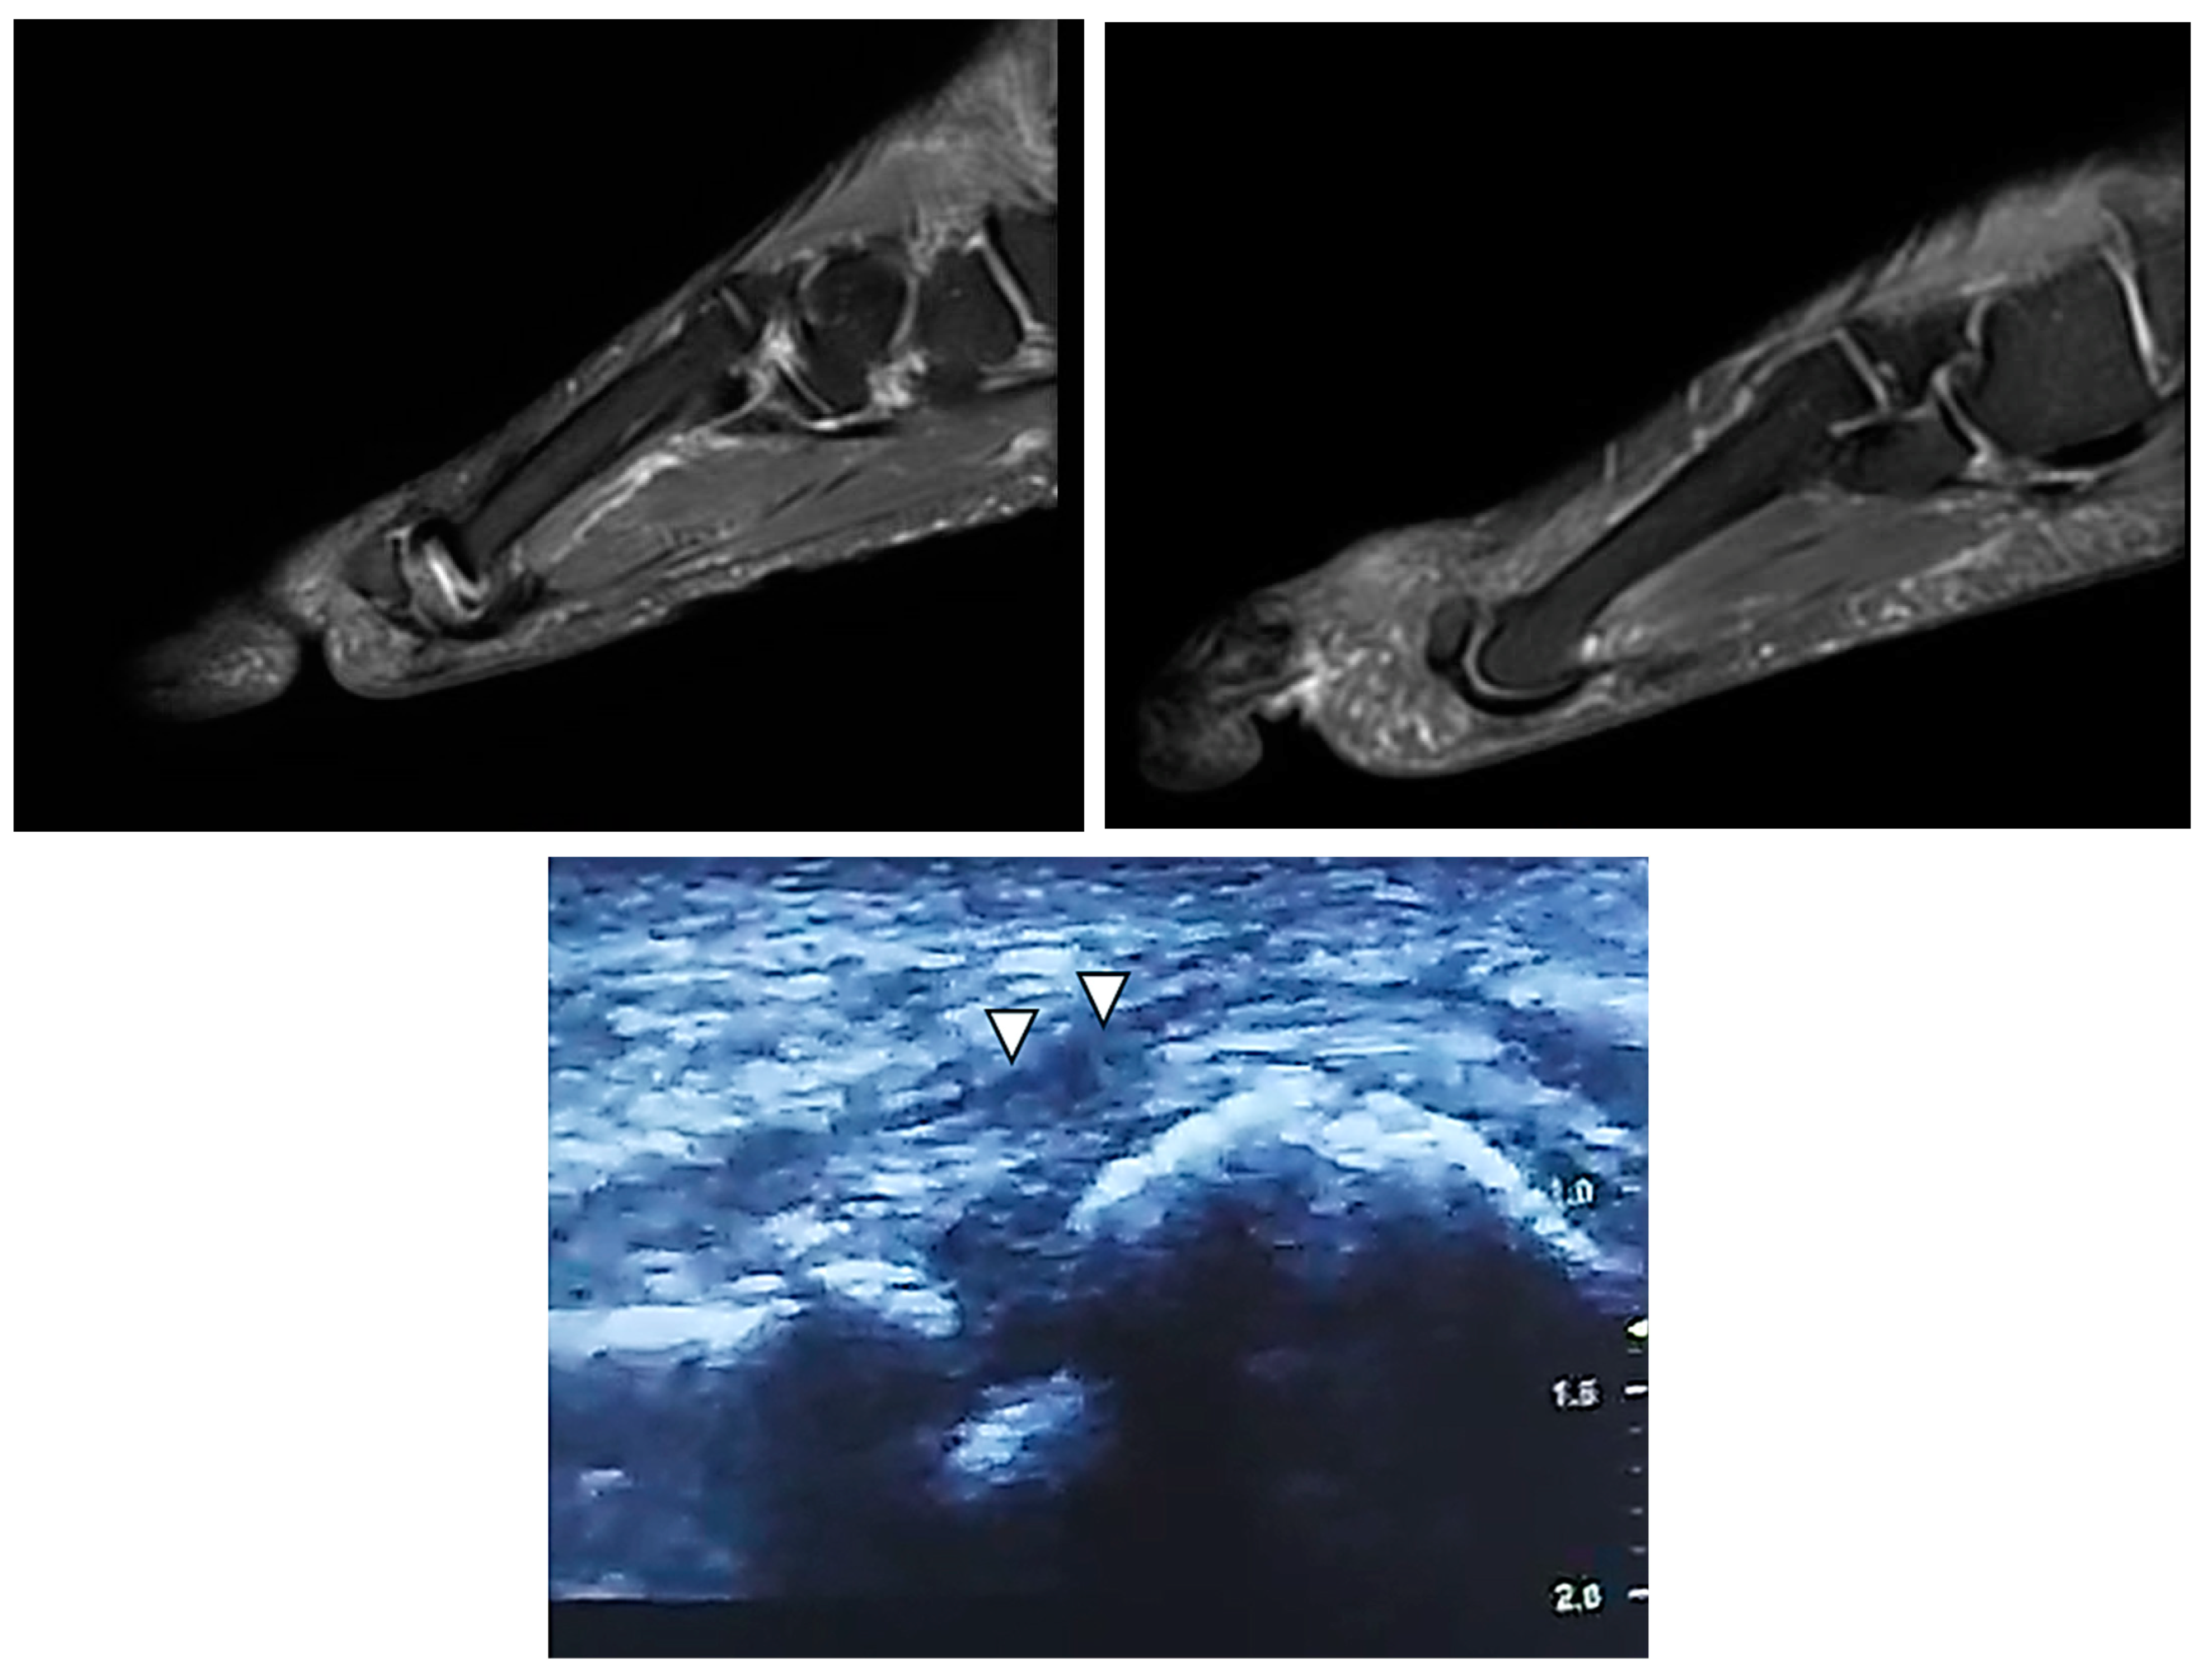

2.1. Case 1

2.2. Case 2